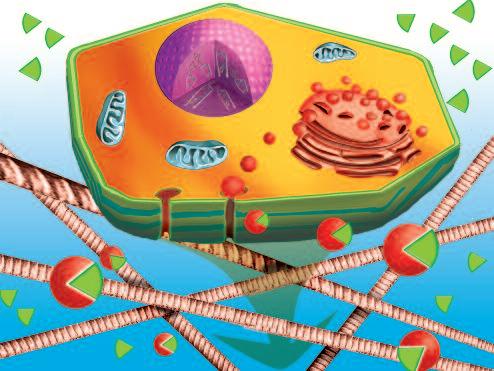

Normalmente, le cellule del nostro corpo sono inserite in una rete di collagene e di altre molecole del tessuto connettivo che le mantengono al loro posto. Affinché le cellule tumorali possano crescere, divenendo un tumore, e possano diffondersi in tutto il corpo, è necessario fendere questo isolamento del tessuto connettivo. A questo fine, ogni cellula del cancro produce ‘forbici biologiche’, ovvero degli enzimi proteolitici in grado di digerire il tessuto connettivo che circonda le cellule tumorali.

Una delle più importanti molecole secrete dalle cellule tumorali in grandi quantità sono gli enzimi a ‘forbice’ che digeriscono il collagene. Sono aggiunti graficamente a questa immagine, sotto forma di strutture simili ad un ‘pacman’ rosso.

Naturalmente questi sfere, nella vita reale, sono molecole biologiche, proteine, che hanno la capacità di tagliare le fibre di collagene e di altre molecole del tessuto connettivo. L‘immagine sopra mostra che non c’è un solo tipo di 'pacman' ovvero di queste molecole, ma

Digestione del tessut o connet tivo del tessuto connetti vo diversi tipi, quali il plasminogeno/plasmina e le metalloproteasi (strutture colorate tridimensionali). Queste molecole migliorano il loro effetto distruttivo attivandosi reciprocamente in forma di reazione a catena in cascata.

Al fine di muoversi attraverso il tessuto connettivo, una cellula deve essere in grado di sciogliere temporaneamente i tessuti circostanti, il collagene e le fibre elastiche. La migrazione cellulare attraverso tessuto denso richiede che queste cellule secernano enzimi, ‘forbici biologiche’, in grado di sciogliere il collagene circostante. Queste molecole proteiche sono note come enzimi che dissolvono il tessuto connettivo o, in breve, enzimi che digeriscono il collagene (collagenasi).

Per facilitare la comprensione, in tutto il libro continueremo a simboleggiare le collagenasi come sfere rossi o ‘pacman’.

Nella pagina a fianco si vede la produzione di enzimi che digeriscono il collagene all'interno di una cellula (figura A). Questi enzimi vengono poi secreti nell‘ambiente di questa cellula dove ‘attaccano’ e digeriscono le fibre di collagene circostanti. Questo processo consente di creare delle ‘scappatoie’ all'interno della fitta rete di tessuto connettivo e di passarvi attraverso (figura B).

Ogni tumore è circondato da una rete di piccoli vasi sanguigni (i capillari). Con l‘aiuto di enzimi che dissolvono il collagene, cellule tumorali individuali possono ‘forare’ il muro di questi capillari ed entrare nel flusso sanguigno Una volta all'interno del vaso sanguigno, le cellule tumorali vengono trasportate dal flusso di sangue, proprio come i globuli rossi o bianchi, e raggiungono altri organi.

Poiché queste cellule tumorali producono ancora grandi quantità di enzimi che assimilano il collagene, sono ora in grado di lasciare di nuovo il flusso sanguigno e penetrare nel tessuto polmonare. Qui le cellule tumorali continuano a moltiplicarsi e svilupparsi in un tumore secondario, una metastasi

Il corpo di questa cellula tumorale in migrazione si espande nella direzione del suo movimento all’interno del tessuto. Può formare una struttura ‘tentacolare’ che trascina la cellula tumorale lungo la superficie, in questo caso, di un vaso sanguigno.

Gli enzimi che digeriscono il collagene sono aggiunti per illustrare il processo mediante il quale qualsiasi ostacolo sul cammino di questa cellula tumorale viene superato.

È interessante notare che la natura stessa ci fornisce due grandi gruppi di molecole che possono bloccare il meccanismo di dissoluzione del collagene. Il primo gruppo è rappresentato un blocco enzimatico intrinseco al corpo che può inibire l’azione degli enzimi proteolitici che digeriscono il collagene in pochi istanti. Il secondo gruppo di sostanze che bloccano gli enzimi proteolitici può essere presente nella nostra dieta eventualmente integrata. Il micronutriente più importante è l'aminoacido naturale L-lisina. Una quantità sufficiente di lisina, sotto forma di supplemento dietetico, può bloccare i siti di ancoraggio ai quali le collagenasi si legano alle molecole del tessuto connettivo. La lisina, quindi, impedisce a questi enzimi di dissolvere il tessuto connettivo in modo incontrollabile.

La pagin a a fianco i llustra la capacit à della lisina di inibire gli enzimi proteolit ici che d igeriscono il collagen e, la d emolizio ne inco ntro llata delle sue fibre e, di conseguenza, o stacol are la diffusione d el cancro .

La lisina occupa i ‘siti di ancoraggio’ in cui le collagenasi normalmente si legano alle molecole del tessuto connettivo in modo da digerirle. Una volta che la lisina occupa questi ‘siti di ancoraggio’, le collagenasi hanno meno presa sulle fibre di collagene e il degrado del tessuto è limitato

L'attività degli enzimi che digeriscono il collagene può essere bloccato in due modi: con le molecole inibitrici del corpo (proteine enzimatiche) e con inibitori naturali forniti nella dieta, quali la lisina.

Gli inibitori interni del corpo formano la prima linea di difesa che assicura l’equilibrio tra il degrado e la nuova formazione di collagene e tessuto connettivo. Nell’illustrazione della pagina a fronte, i ‘blocchi’ dell'enzima prodotti dal corpo sono rappresentati da triangoli blu.

Le molecole di lisina, visualizzate in verde, hanno lo stesso obiettivo. Formano la seconda linea di difesa, pronte a intervenire quando i sistemi del corpo sono insufficienti Questi ‘blocchi’ dietetici non hanno effetti collaterali, anche se assunti in grandi quantità cospicue.